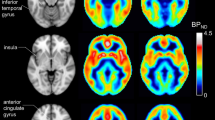

Baseline measures for methylation status of the FMR1 gene, mRNA and FMRP showed considerable heterogeneity in the study population (Figure 2). Correlations were observed between FMR1 methylation status and mRNA levels (Pearson correlation coefficient (r) of −0.74), and between FMR1 methylation status and FMRP levels (r=−0.64) but not between mRNA and FMRP concentrations (r=0.39; p<0.001 for all paired data sets).

Biomarker analysis of FMR1 promoter methylation, FMR1 mRNA and FMRP in study patients. The figure shows the frequency distribution of biomarker data. Data of patients were distributed over 50 bins and frequency of appearance is depicted on the Y-axis. Male-derived samples are in solid black and Female in blue bars. (a) Levels of FMRP in whole blood in pM. Most of the male patients had no detectable levels of FMRP in the blood (0 pM). (b) Levels of FMR1 mRNA expressed as delta CT values. Note that delta Ct values over 6 are not considered to represent quantifiable levels of mRNA but rather unspecific noise as judged by the CP curves. (c) Methylation of the FMR1 promoter expressed in percent methylation of analyzed methylation sites.

The relationship of biomarker subgroups and the effects of basimglurant were also explored. Biomarker positive was defined by FMR1 methylation greater than 73.95% of the analyzed methylation sites, mRNA ΔCT count greater than 1.975, or FMRP concentrations less than 0.146 pM. The analysis showed that both biomarker-positive and -negative subgroups did not differ significantly between placebo and basimglurant in the assessment of change from baseline to week 12 for the ADAMS total score (Table 2). In the FMR1 methylation negative (<73.95%) subgroup, patients who were randomized to the placebo arm improved significantly (p=0.019) compared to patients in the basimglurant 0.5 mg dose arm. This improvement may be driven by the change in ADAMS total scores from the female patients in the placebo arm.